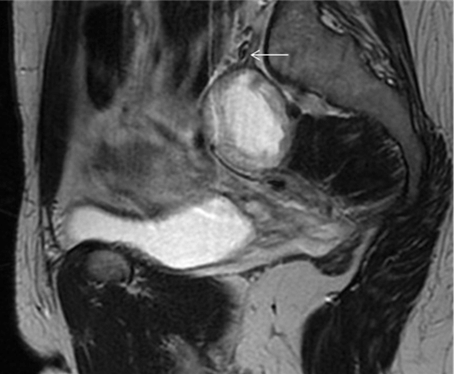

Computed tomography (CT) scan of the pelvis reported the presence of a 4.5 cm nodular lesion, located deep in the right pelvic region (Figure 1). Magnetic resonance imaging (MRI) scan showed a dependent right sciatic nerve lesion (Figure 2). The lesion contacted with the anterior surface of the sacrum and medially displaced the right hypogastric artery (Figure 3).

Figure 2: Magnetic resonance imaging T2-weighted sagittal image (Fast Spin Echo): Well-circumscribed fusiform dependent sciatic nerve mass (arrow). Magnetic resonance imaging showing an isointense mass with a hyperintense center and a thin hypointense capsule.

Figure 3: Magnetic resonance imaging T1-weighted axial image: A well-defined hypointense mass (arrow) adjacent to the hypogastric vessels (arrow) is noted.

Pelvic schwannomas are usually diagnosed incidentally, as solitary lesions, although some patients report abdominal pain or chronic sciatica. In case of chronic sciatica with no signs of radicular compression at MRI, the sciatic nerve must be radiologically examined all along its course [6]. Preoperative imaging tests are useful in determining the size, location and relationship of the lesion with neighboring tissues. Computed tomograhpy (CT) scan usually reveals a well-circumscribed lesion, with round or oval slight enhancement. Schwannomas are seen as isointense lesions on T1-weighted MRI and hyperintense on T2-weighted MRI scan. However, many schwannomas may show mix intensity on both T1- and T2-weighted images if they are associated with cystic degeneration, necrosis and (or) hemorrhage within the tumor [7]. Neurofibromas should be considered in the differential diagnosis. An eccentric association with the nerve is suggestive of a schwannoma.